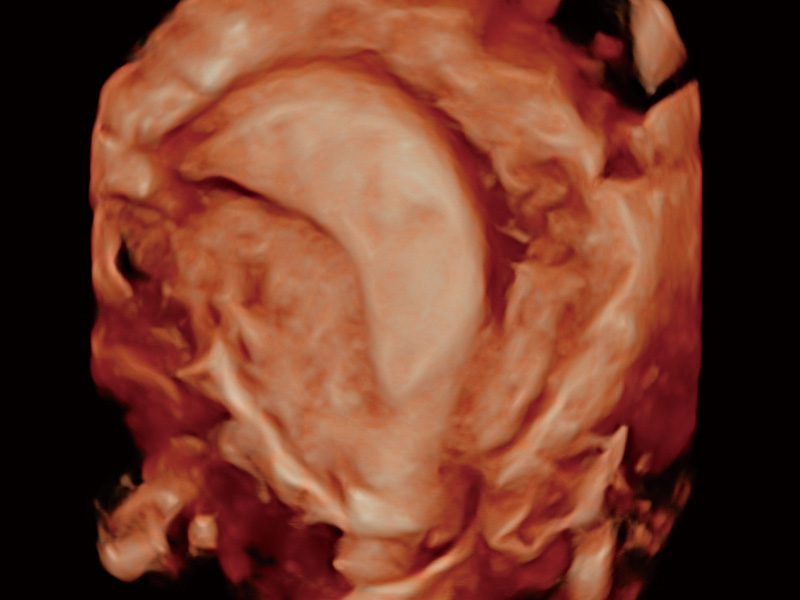

“生育问题”即关系民族复兴,也关系亿万家庭的幸福。随着婚育年龄推迟、社会压力增加等因素,越来越多人群也面临着“生不出、生不好”的问题。辅助生殖作为治疗不孕不育最有效的方法之一,也逐渐成为育儿新希望。而超声检查能为生殖需求人群的初诊评估提供宝贵的信息。 P20 Elite是百老汇电子游戏官网匠心打造的一款生殖应用型彩超。她继承百老汇电子游戏官网高端极光平台,突破性地将多款新型芯片及硬件模块进行整合,均衡了高端系统性能与小巧灵动机身。P20 Elite卓越的图像质量搭载专科探头,旨在为您提供全面的辅助生殖解决方案。

P20 Elite配备了丰富的生殖探头群和临床应用功能,在卵泡监测、穿刺取卵、胚胎移植、妊娠确认等领域,为生殖需求人群提供了新的临床机会,重新定义高端超声如何应用于生殖健康检查。